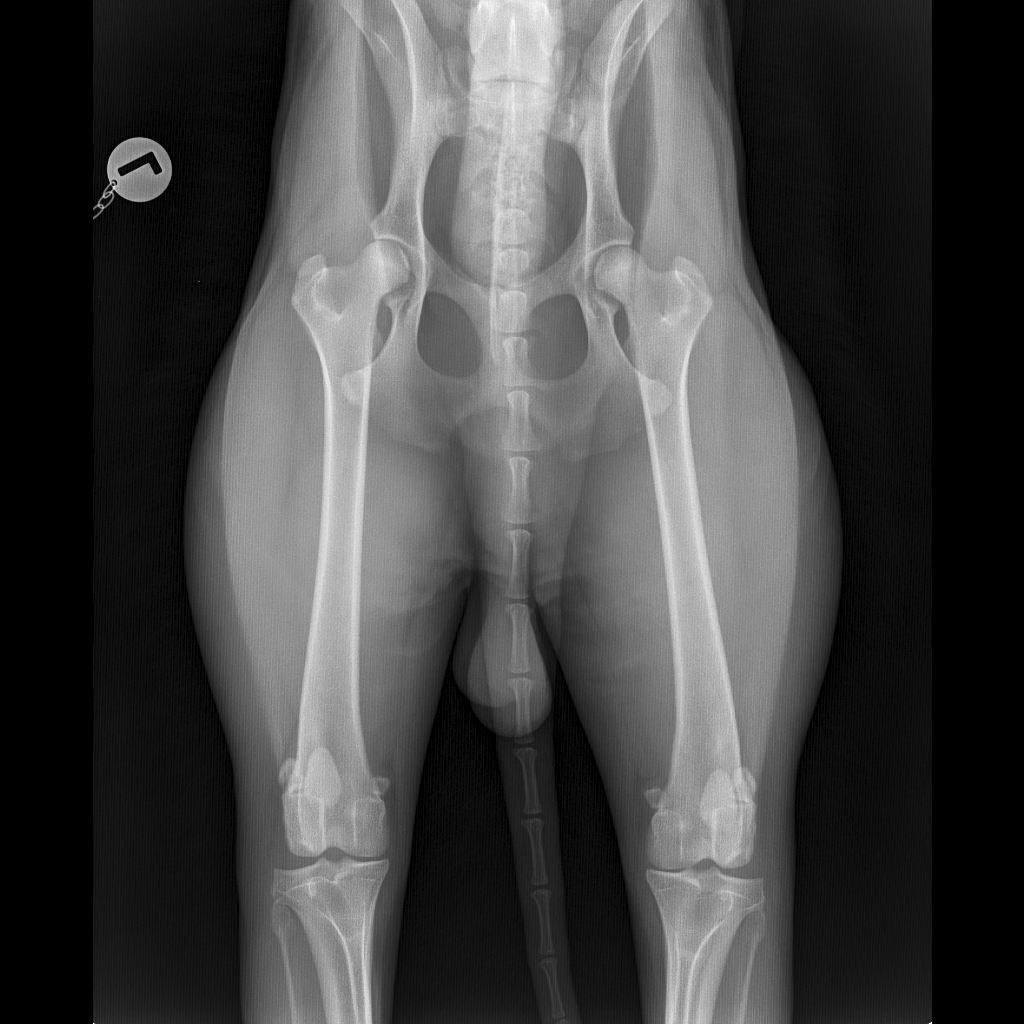

- Digitales Röntgen (HD, OCD, ED): Hochleistungsröntgen mit digitaler Entwicklung